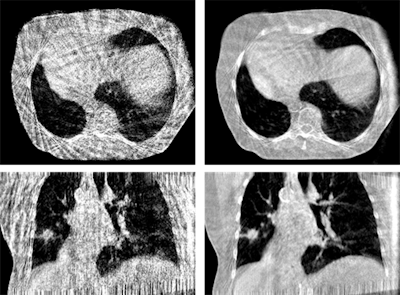

To date, all state-of-the-art motion management approaches in CBCT image reconstruction have a number of limitations; for example, immobilization devices (e.g., head frames) do not exclude patient motion entirely, and despite their rigidity and patient discomfort still permit for residual involuntary patient motions, such as swallowing or residual flexibility (figure 2).

Typically, such nonperiodic motion affects only a subset of the x-ray projections but impairs overall image quality. For abdominal therapy planning using CBCT, prospective gating or acquiring a single or a sequence of breath has been demonstrated to improve image quality. In temporally resolved CBCT, clinically available algorithms are usually based on retrospective phase gating. This implies that each 3D phase image is reconstructed from a subset of the x-ray projections, and, therefore, most likely suffers from sparse data artifacts. However, MoCo reconstruction (figure 3) provides the unique advantage to use all projections for the image reconstruction of each phase.